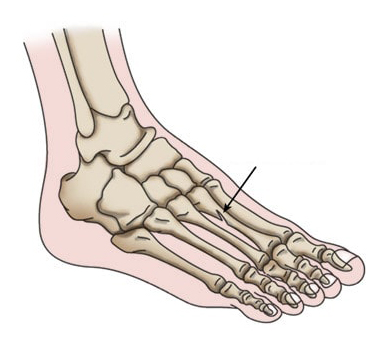

stress fracture

Arrow indicates a stress fracture of a metatarsal bone in the foot.